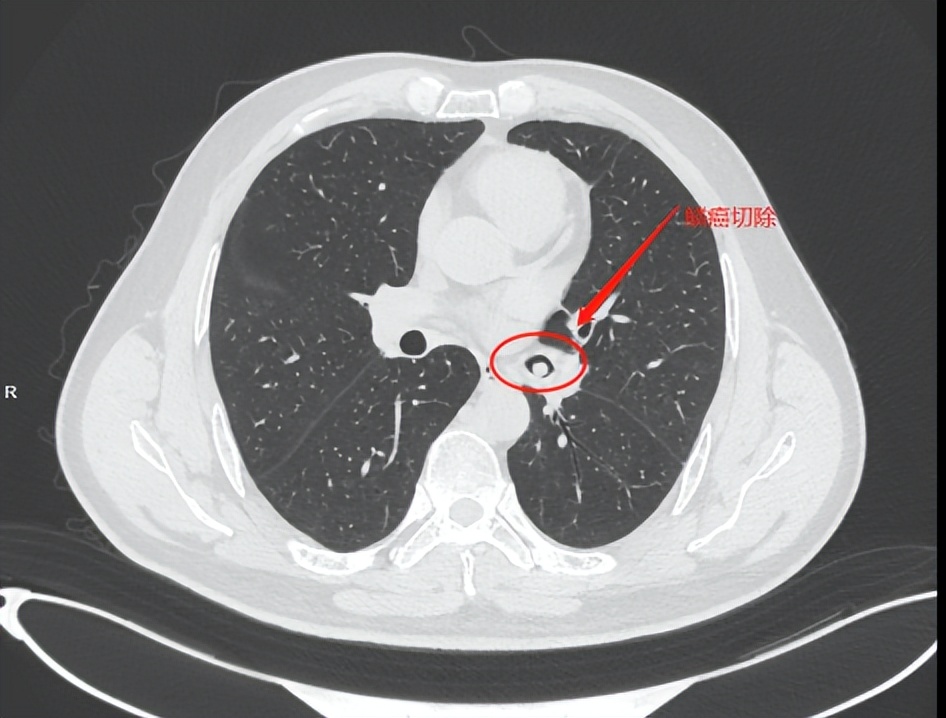

病患情况:40余年吸烟史,Ⅱ型糖尿病,2022年2月体检发现右肺上叶可见斑点状、磨玻璃样高密度结节灶,左侧主支气管内可见结节灶,直径约0.8cm(4月份支气管镜检测为鳞癌),2022年4月因咳嗽住院,经过胸部CT(128肺+心脏)检测,右肺上叶散在少许斑片状磨玻璃结节灶,边缘模糊。左肺下页支气管开口区见结节状软组织密度灶。经过支气管镜取病理检测,确诊为乳头状鳞状细胞癌(非角化)。

2022年4月底我们在省会肿瘤医院进行了住院检查(CT胸部平扫+增强),发现右肺上叶尖段见磨玻璃结节,大小为8mm*7mm,CT值为-738.4HU,左肺下叶外基段见5mm*5mm小磨玻璃结节,CT值为-679.2HU(该结节已被手术切除)。之后做过PET-CT检查显示未转移。主治大夫确定手术方案为袖状切除肺左下叶,目前我父亲已做完手术出院恢复,病理结果显示低分化乳头状鳞状细胞癌,出院诊断为左肺下叶癌(PT1AN0M0),区域淋巴结状态:支气管周(0/1),7组(0/2),9组(0/1),10组(0/1),11组(0/3),我申请做了肿瘤8基因检测(实测51种基因)和PD-L1伴随诊断检测,目前结果未出。